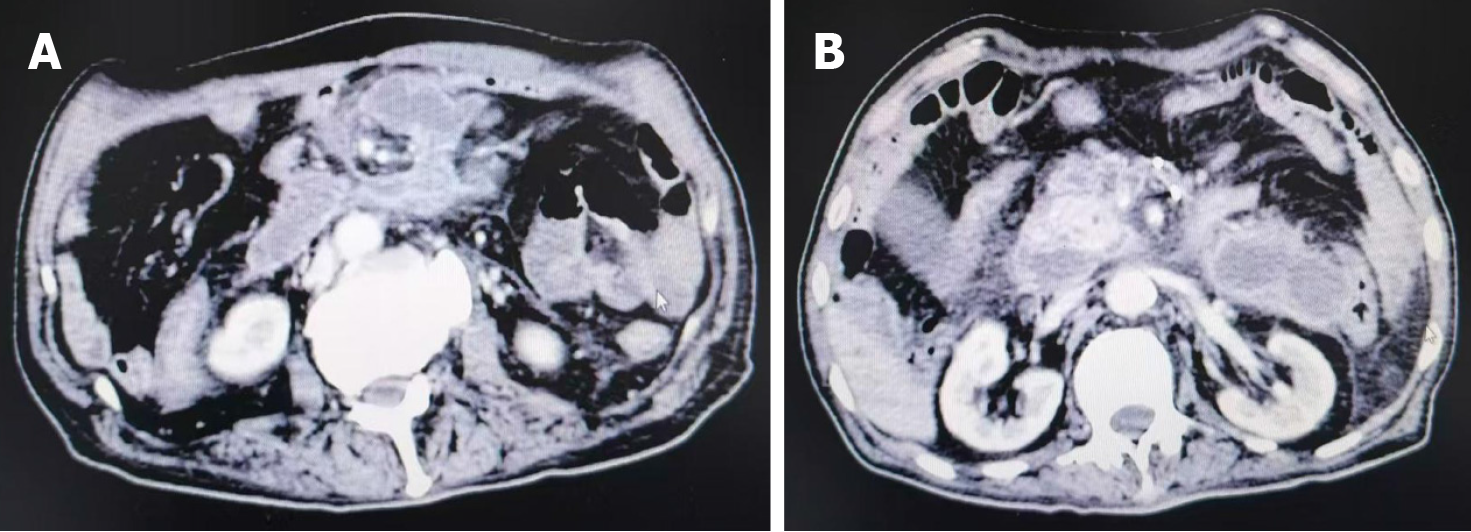

Figure 4 Post-percutaneous drainage fragmentations of necrotic collections.

A: Cross-sectional view of an infected necrotizing pancreatitis lesion after percutaneous drainage; B: Another view from the same post-procedural patient.